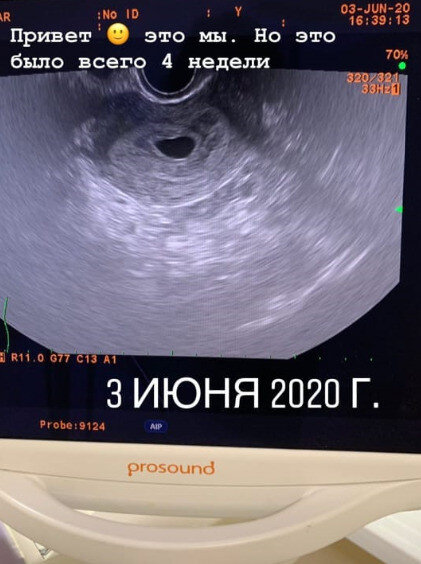

На днях блогер Мария Балмашева призналась, что забеременела, несмотря на поставленный ранее диагноз — бесплодие. Женщина ждет ребенка от своего пасынка. У пары все серьезно, они даже собираются пожениться. При этом Марина уверена, что 15-летняя разница в возрасте не помешает им построить счастливую семью. История 35-летней Балмашевой больше напоминает бразильский сериал. Женщина влюбилась в... сына своего супруга Алексея — Вову. И через некоторое время стала жить с ним. Много лет Марина не могла иметь детей, но недавно стала известна радостная новость. «Надоело скрываться. Знаю, что срок еще маленький, УЗИ с сердечком еще впереди. Но хочу, чтобы вы это знали. Все возможно в этом мире. Нам четыре недели, и да — именно поэтому мы решили пожениться», — сообщила она в Instagram три дня назад. Помимо этого, блогер показала фото с УЗИ, на котором, конечно, пока еще нельзя рассмотреть очертания плода. Марина уверяет подписчиков, что пока у нее нет токсикоза, но определенные пищевые прист

Марина Балмашева, забеременевшая от пасынка, опубликовала фото УЗИ